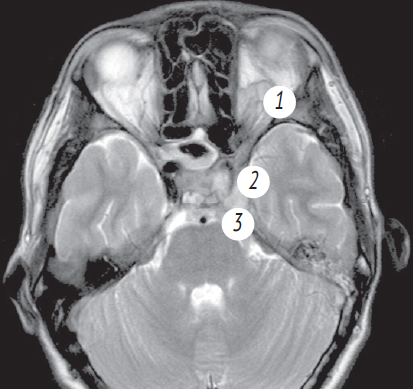

Рис. 5. Магниторезонансная томография головы от 10.11.2021: правосторонний сфеноидит, тромбоз кавернозного синуса слева. Слева — коронарная проекция в режиме Т2. Тотальное затенение правой половины пазухи клиновидной кости, сужение кавернозного синуса слева; справа — аксиальная проекция в режиме Т2. Признаки тромбоза кавернозного синуса слева

Fig. 5. Magnetic resonance imaging of the head from 10.11.2021: right-sided sphenoiditis, thrombosis of the cavernous sinus on the left. Left: coronal projection in T2 mode. Total shading of the right half of the sphenoid sinus, narrowing of the cavernous sinus on the left; right: axial projection in T2 mode. Signs of thrombosis of the cavernous sinus on the left

Рис. 6. Магнитно-резонансная томограмма головного мозга. Признаки тромбоза кавернозного синуса. 1 — Венозный застой в ретробульбарной клетчатке; 2 — cужение просвета сифона внутренней сонной артерии слева; 3 — неоднородность структуры

Fig. 6. Signs of cavernous sinus thrombosis on magnetic resonance imaging of the brain. 1 — Venous congestion in the retrobulbar tissue; 2 — narrowing of the lumen of the siphon of the internal carotid artery on the left; 3 — structure heterogeneity